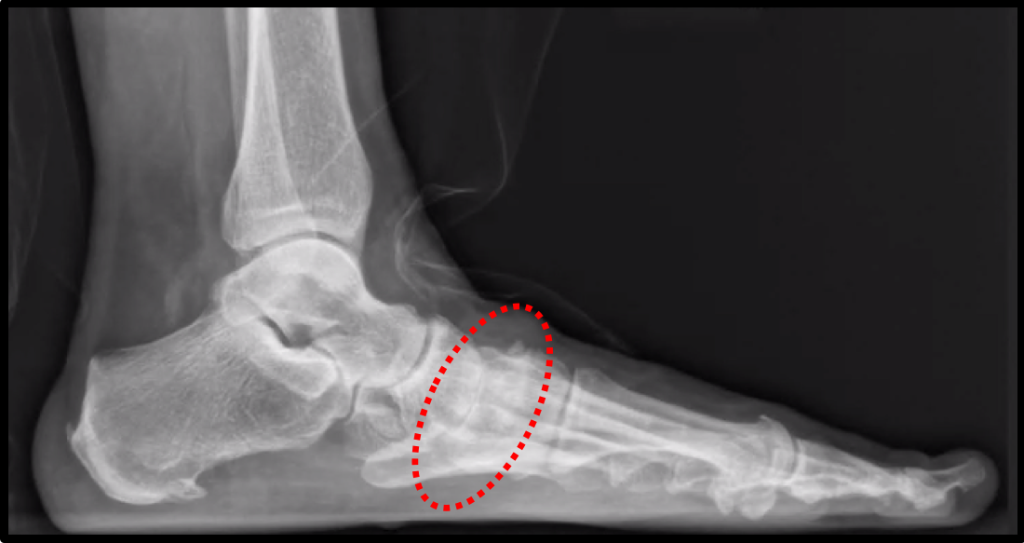

Exames de Imagem:

- Radiografias (Raio-X): São os primeiros exames solicitados. Eles podem revelar o estreitamento do espaço articular (indicando perda de cartilagem), a presença de osteófitos (bicos de papagaio) e alterações na estrutura óssea.

- Ressonância Magnética (RM) ou Tomografia Computadorizada (TC): Podem ser solicitadas para avaliar a cartilagem, identificar edemas ósseos e visualizar outras estruturas em maior detalhe, ajudando a planejar o tratamento.